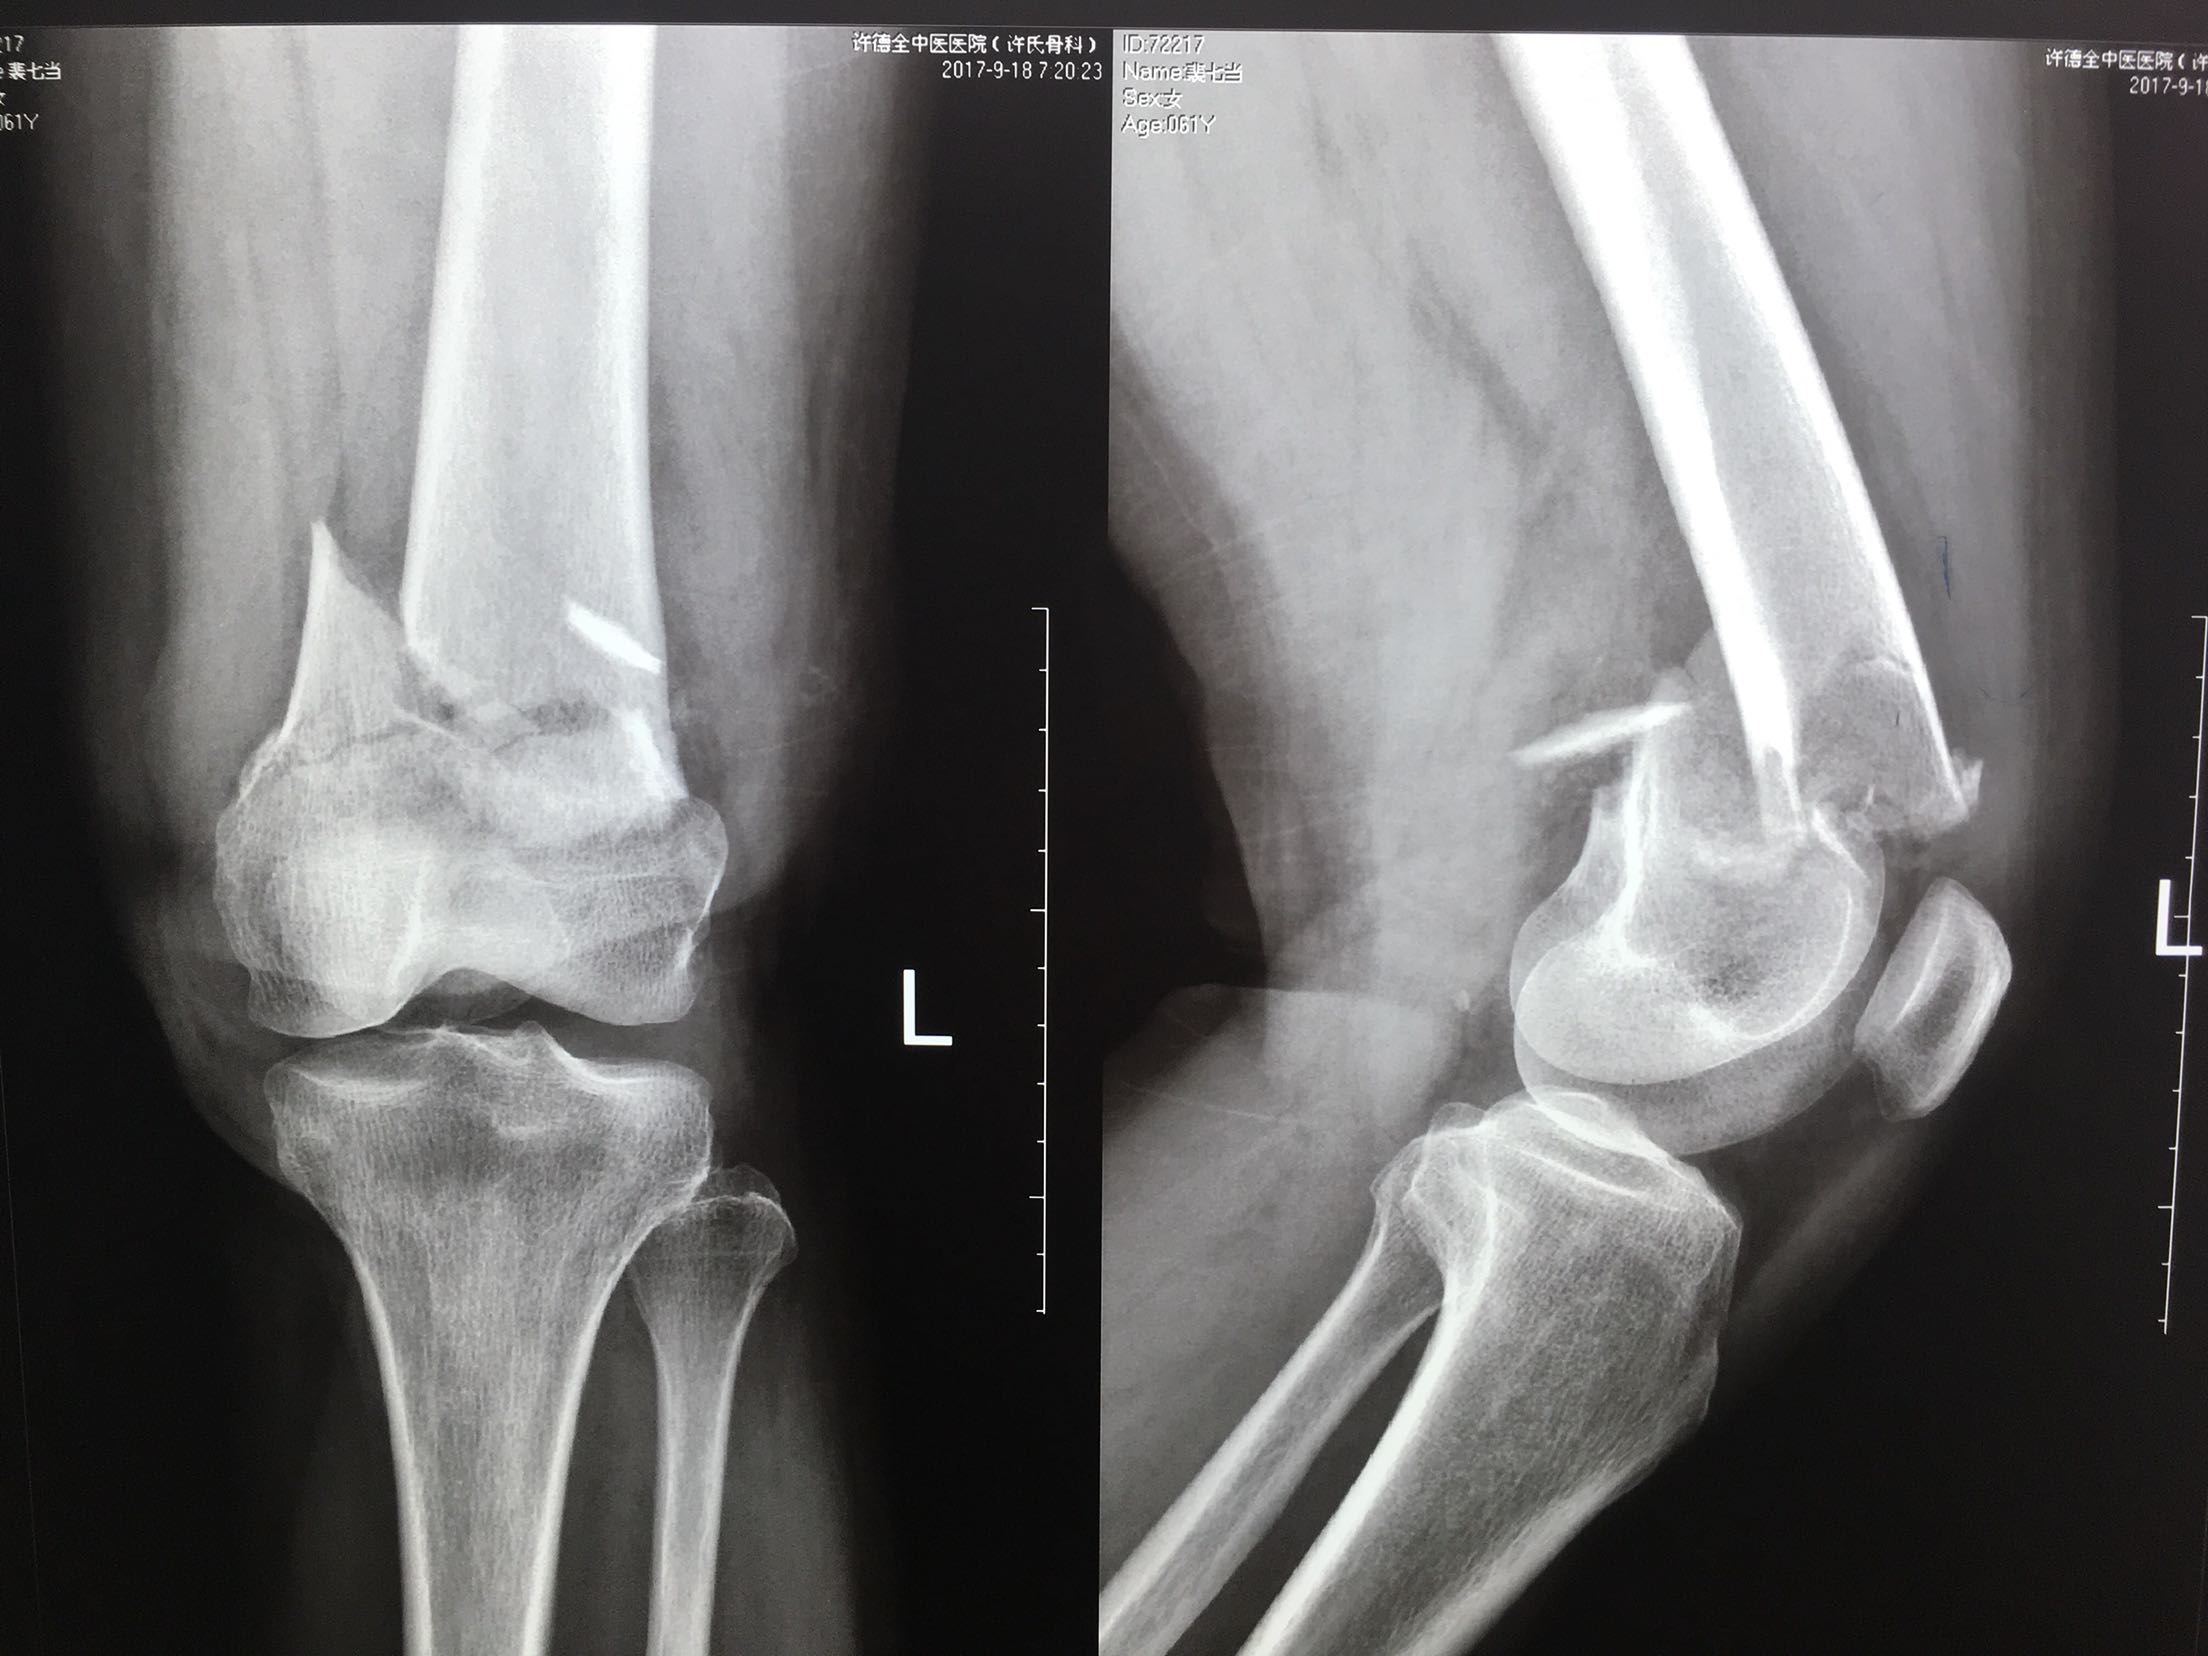

患者,女性,61岁,摔伤后左大腿疼痛,畸形,活动受限1小时。

左大腿远端局部肿胀,环形压痛,可及骨檫音,异常活动,

远端血运感觉正常。

完善检查,急诊在局麻下行胫骨结节骨牵引术。术后一周,病情平稳,在腰麻下行切复内固定术,考虑骨折粉碎,骨质疏松,拟行双钢板固定。术后抗炎,对症治疗,嘱咐一周后早期膝关节微动锻炼。